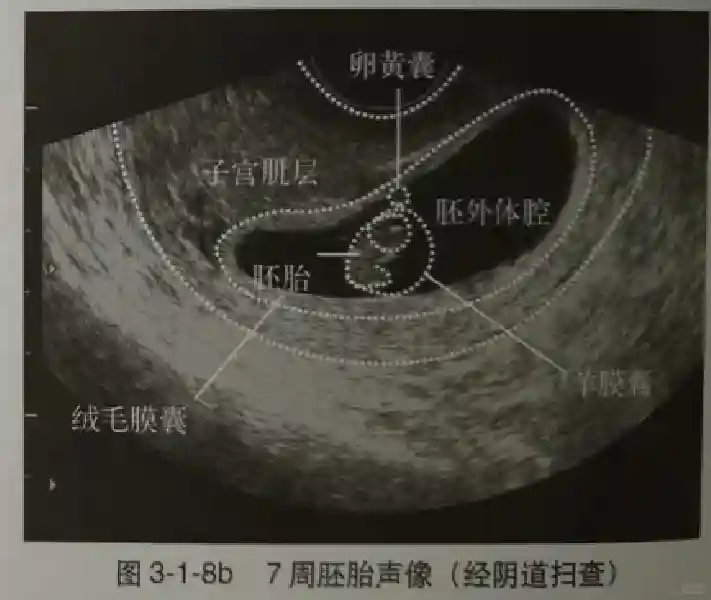

2️⃣卵黄囊:是妊娠囊内第一个解剖结构,直径<7mm。表现为小环状,中央为无回声,囊壁薄,内透声好。卵黄囊位于胚胎旁胚外体腔内。卵黄囊通常在孕5-6周时出现,5-10周稳步增长,一般不超过7mm,至12周消失。妊娠囊的大小与卵黄囊之间有一定关系,妊娠囊平均直径> 8 mm 时,经阴道超声均应显示卵黄囊,妊娠囊平均直径> 18 mm 时,经腹超声均应显示卵黄囊。

3️⃣胚胎:胚胎通常在6-7周时可以为超声显示,起初为胎芽,表现为卵黄囊一侧局部组织增厚,达到1 -2 mm 时才有可能为超声测量出来。达4-5mm时可见胎心搏动,相应孕周为6-6.5周,妊娠囊大小为13-18mm。胚芽长度≥7㎜时仍未见心管搏动,提示胚胎停止发育。胚胎的出现和妊娠囊直径的关系:妊娠囊直径> 16 mm 时,经阴道超声应显示胚胎。妊娠囊直径> 25 mm 时,经腹超声均应显示胚胎。

5️⃣羊膜:早孕期羊膜囊菲薄,超声常不能显示。孕7周以后加大增益或者用高频超声可以显示羊膜。羊膜囊位于绒毛膜内,胚胎位于羊膜囊内。随着胚胎增长,羊水增多,羊膜囊增大,孕12-16周时,羊膜与绒毛膜全部融合,胚外体腔消失。宫腔线一侧内膜内一圆形增强回声区,中央有小囊状液性暗区,宫腔线局部突起变形,称蜕膜内征,用于判断早早孕。

5️⃣羊膜:早孕期羊膜囊菲薄,超声常不能显示。孕7周以后加大增益或者用高频超声可以显示羊膜。羊膜囊位于绒毛膜内,胚胎位于羊膜囊内。随着胚胎增长,羊水增多,羊膜囊增大,孕12-16周时,羊膜与绒毛膜全部融合,胚外体腔消失。宫腔线一侧内膜内一圆形增强回声区,中央有小囊状液性暗区,宫腔线局部突起变形,称蜕膜内征,用于判断早早孕。#超声 #早孕检查 #妊娠